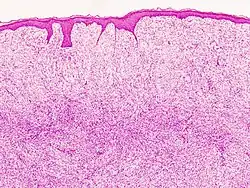

| Histopathological image of dermatofibrosarcoma protuberans. Local recurrence long after the first excision. H&E stain | |

Monotonous, plexiform structure of tumour